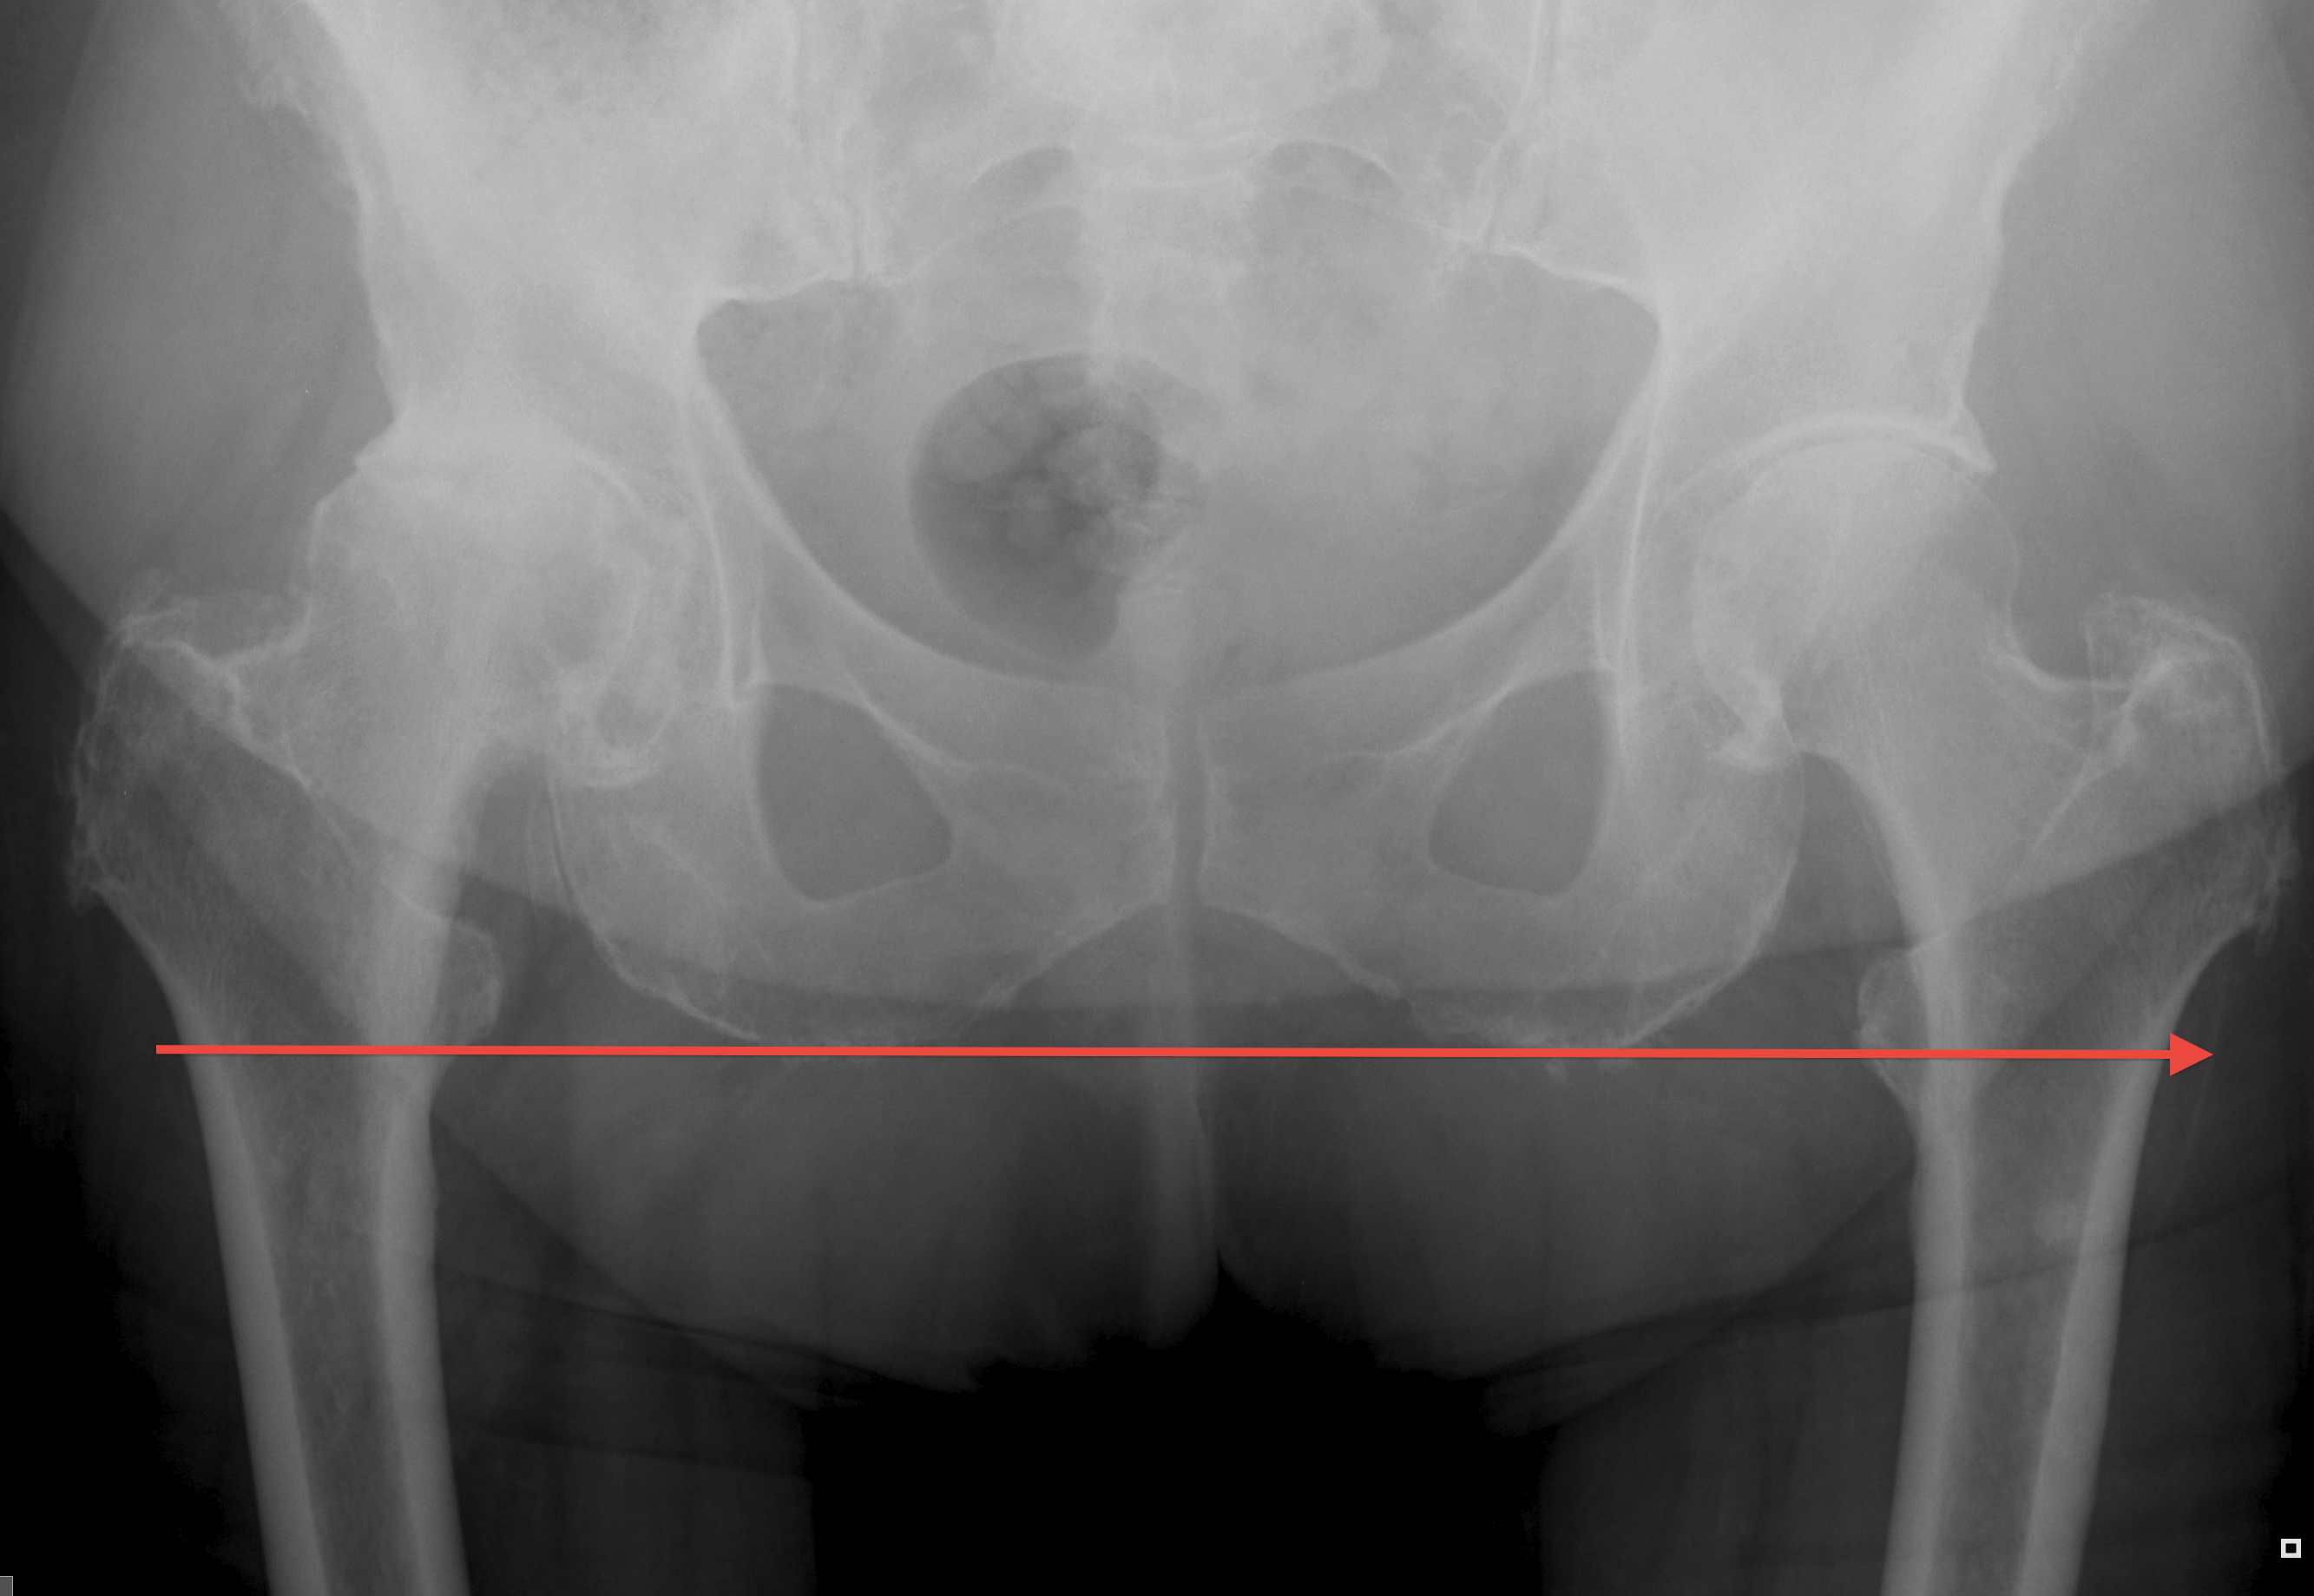

Pelvic landmarks

- inferior aspect of ischial tuberosities

- tear drop

- center of rotation

Femoral landmarks

- lesser tuberosity

1. Leg to leg comparison

Careful patient positioning

- ASIS perpendicular to floor and patient stable

- place both legs in same position i.e. flexion / adduction

- supine - palpate medial malleolus